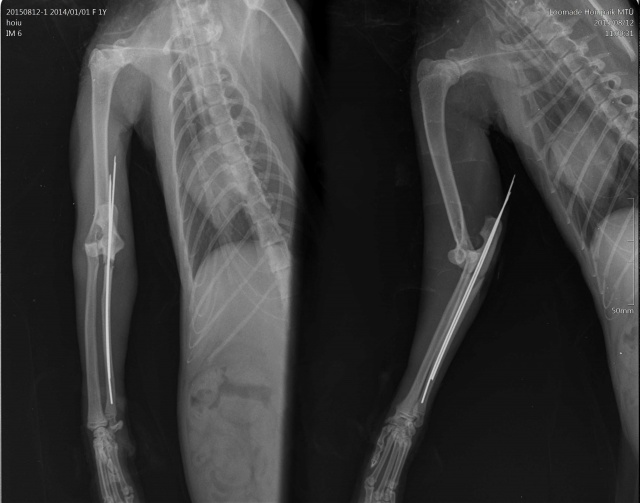

Kass on opereeritud! - Кошка прооперирована.

Диагноз:

- вывих локтевого сустава

- перелом локтевой кости

- межмыщелковый перелом плеча(?)